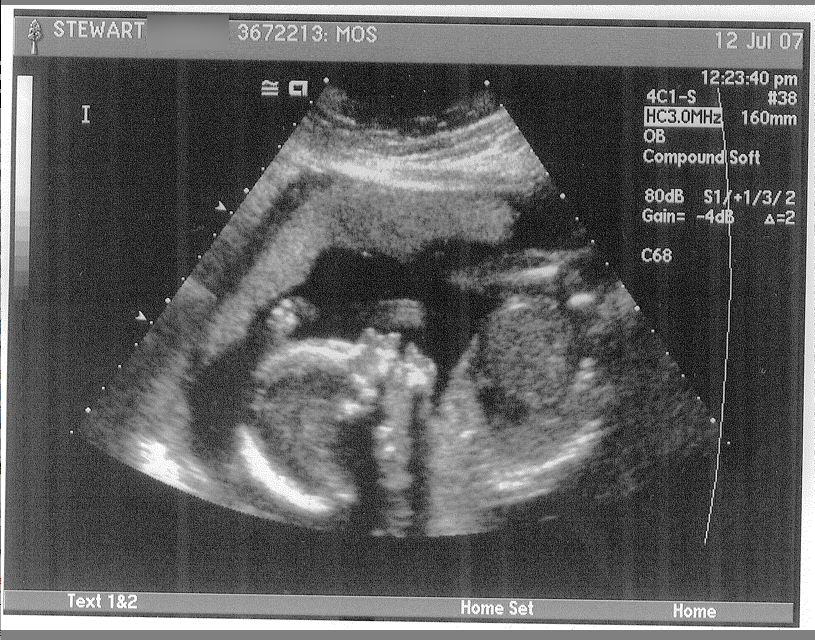

That’s right, ladies and gents: Numero Dos is on the way, and boy ain’t he/she a beaut? (We’re going to be surprised as to the sex as we were with Will).

Baby is healthy, although the ultrasound tech said they’re a little on the small side. They said the same thing about Will, and look how he turned out…CORRECTION: On the small side for us. Which means they’re still big. *grin*